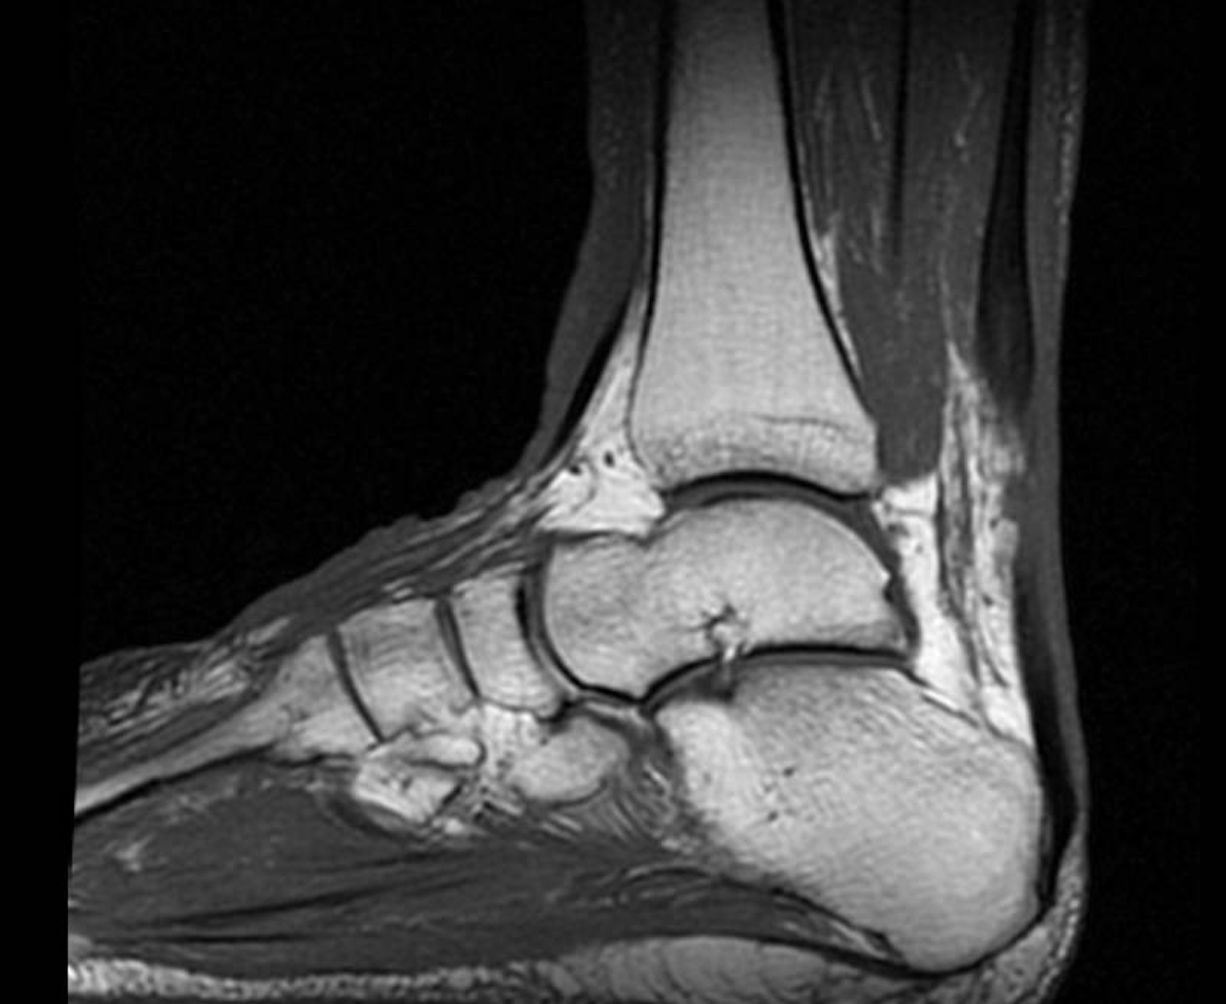

MRI BLOG Partial Tears of Achilles Tendon Achilles Injury X Ray Achilles tendon is completely ruptured at the myotendinous junction,. an achilles tendon rupture is an injury that is usually painful and likely to affect your ability to walk. the patient had sports injury one day before and presented with sudden onset of pain and swelling in the posterior. the achilles tendon is commonly affected by both chronic. Achilles Injury X Ray.

Achilles tendon rupture as seen on an MRI YouTube Achilles Injury X Ray Achilles tendon is completely ruptured at the myotendinous junction,. from the case: the achilles tendon is commonly affected by both chronic repetitive overuse and traumatic injuries. the patient had sports injury one day before and presented with sudden onset of pain and swelling in the posterior. an achilles tendon rupture is an injury that is usually. Achilles Injury X Ray.

the patient had sports injury one day before and presented with sudden onset of pain and swelling in the posterior. an achilles tendon rupture is an injury that is usually painful and likely to affect your ability to walk. Achilles tendon is completely ruptured at the myotendinous junction,. achilles tendon ruptures are common tendon injuries that occur due to sudden dorsiflexion of a plantarflexed foot, most. from the case: the achilles tendon is commonly affected by both chronic repetitive overuse and traumatic injuries.